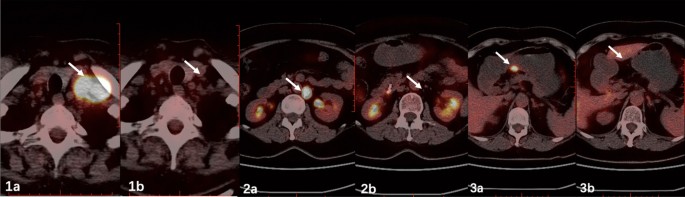

Gastroscopy performed 3 years ago revealed an obvious gastric mass around the gastric antrum which proved to be poorly differentiated adenocarcinoma by cytologic evaluation. The chest CT at the same time showed obvious enlargement of supraclavicular lymph nodes. Afterwards, the patient received 6-course chemotherapy of SOX (S-1 and oxaliplatin) regimen. Contrast-enhanced computed tomography on admission this time revealed the previously enlarged cervical lymph nodes significantly shrank (Fig. 1) and gastroscopy on admission also revealed the previous obvious gastric mass at the gastric antrum had shrank into an ulcer scar at the lesser curvature. Positron emission tomography/computed tomography (PET/CT) showed previous multiple lymph nodes with increased metabolism at the lesser curvature of stomach, para- abdominal aorta and bilateral supraclavicular fossa were no longer obvious on admission (Fig. 2). All of these evidences demonstrated that the patient’s gastric adenocarcinoma achieved complete response after neoadjuvant chemotherapy.

Contrast-enhanced abdominal computed tomography performed 6 months ago suggested dilatation of intra- and extrahepatic bile ducts and the pancreatic duct and the presence of suspicious nodules at the duodenal papilla (Fig. 3). Afterwards, she presented with yellow sclera and skin, choluria and clay colored stool that persisted for 3 months. Laboratory examinations revealed 64.6 μmol/L total bilirubin (normal, 5.1–22.2 μmol/L), 50.0 μmol/L direct bilirubin (normal, 0–6.8 μmol/L), elevated transaminase levels, including 38U/L alanine aminotransferase (normal, 7–40 U/L), 80U/L aspartate aminotransferase (normal, 13–35 U/L) and cholestasis parameters, including 1411U/L γ-glutamyl transpeptidase (normal, 7–45 U/L), 314U/L alkaline phosphatase (normal 50–135 U/L). Tumor markers carbohydrate antigen 19–9 was 58.1U/ml (normal, 0–34 U/ml)while levels of other tumor markers were within normal limits. Magnetic resonance cholangiopancreatography (MRCP) showed the common bile duct and main pancreatic duct were suddenly narrowed in the duodenal ampulla and the upstream bile duct was obviously dilated suggesting the presence of an ampullary tumor (Fig. 4a). Neither Lymph node enlargement nor distant metastasis were found. Endoscopic retrograde cholangiopancreatography (ERCP) showed a bulging protrusion at the ampulla of Vater which was diagnosed on biopsy to be poorly differentiated adenocarcinoma (Fig. 4b). Implantation of bile duct and pancreatic duct plastic stent was performed during ERCP. PET/CT showed an increased metabolic focus of 1.0 × 0.8 cm and SUVmax 4.0 at the duodenal papilla area considered to be malignant lesions, the properties of which still needs to be determined (Fig. 4c). The patient has lost 8 kg for the last 3 months.